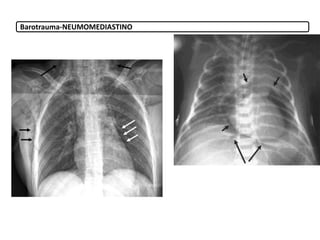

o Barotrauma: Por aumento de la presión en el pulmón (0,5-

– Neumomediastino

Barotrauma-NEUMOMEDIASTINO

9.3. Derivadas dela presión positiva 9. Complicaciones Ventilación mecánica o Barotrauma: Por aumento de la presión en el pulmón (0,5- 30%) (presiones >35- 40 cm H2O) – Neumotórax – Enfisema subcutáneo – Neumomediastino o Volutrauma: Por ventilar con un volumen excesivo. o Atelectrauma: Por abrir y cerrar continuamente sus alveolos. Hay que valorar PIF, pico de flujo inspiratorio, evitando el colapso en espiración. o Biotrauma: respuesta fisiológica al estrés mecánico inducido por la ventilación. o Infecciones: neumonía o Toxicidad por O2